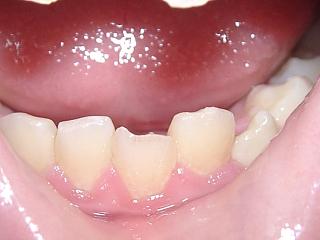

単純性歯冠破折:エナメル質に限局するか、エナメル質および象牙質を含む破折で露髄を伴わないもの (図1)

単純性歯冠破折の場合(図1)

無症状か、軽度の冷温水痛あり。

レジン樹脂などで破折部の修復を行います。